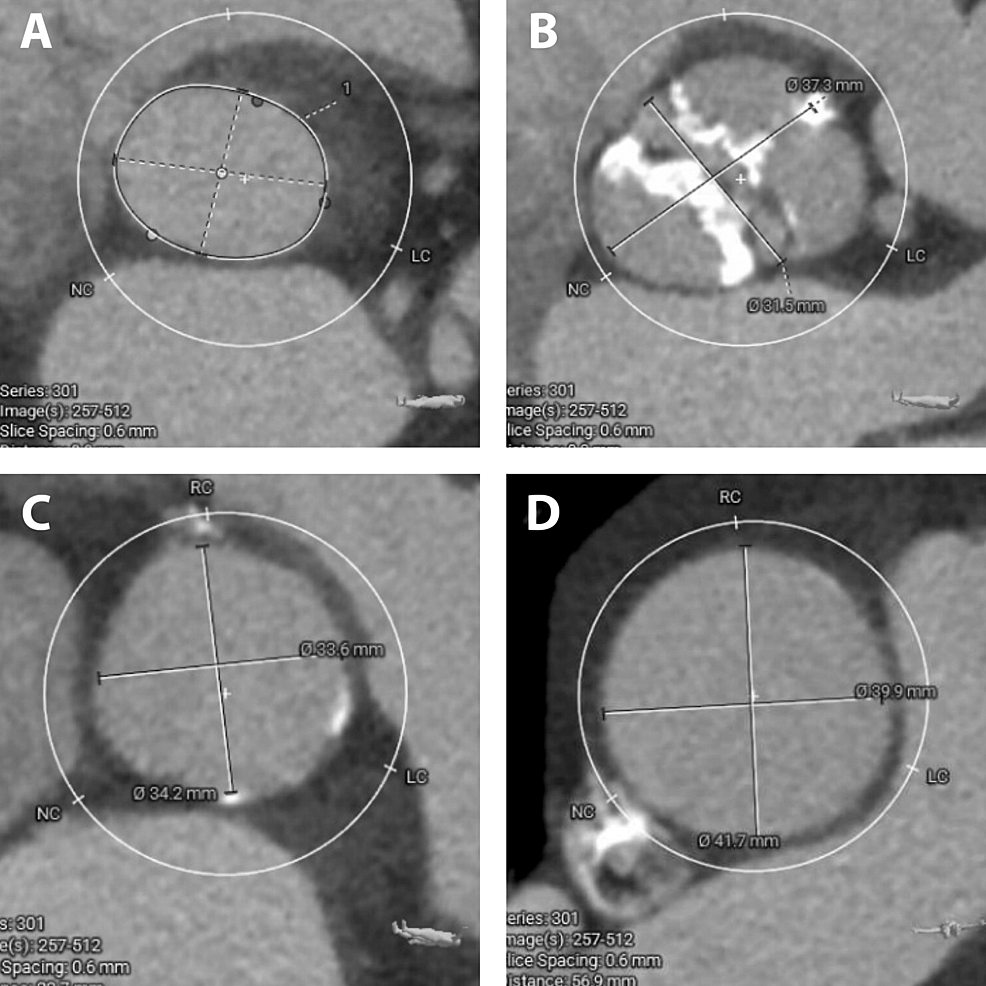

Aortic annulus rupture with fistula to the right ventricle following

Aortic annulus rupture with fistula to the right ventricle following Aortic Valve Replacement Cxr Aortic and mitral valves are the commonly affected by disease. It allows blood to exit the left ventricle (lv) during. The position of the cardiac valves can be inferred on both the pa and. The stenotic aortic valve is repaired by placing a prosthetic valve within the diseased. Despite numerous advancements in transcatheter and surgical aortic valve replacement (avr), hf. Aortic Valve Replacement Cxr.